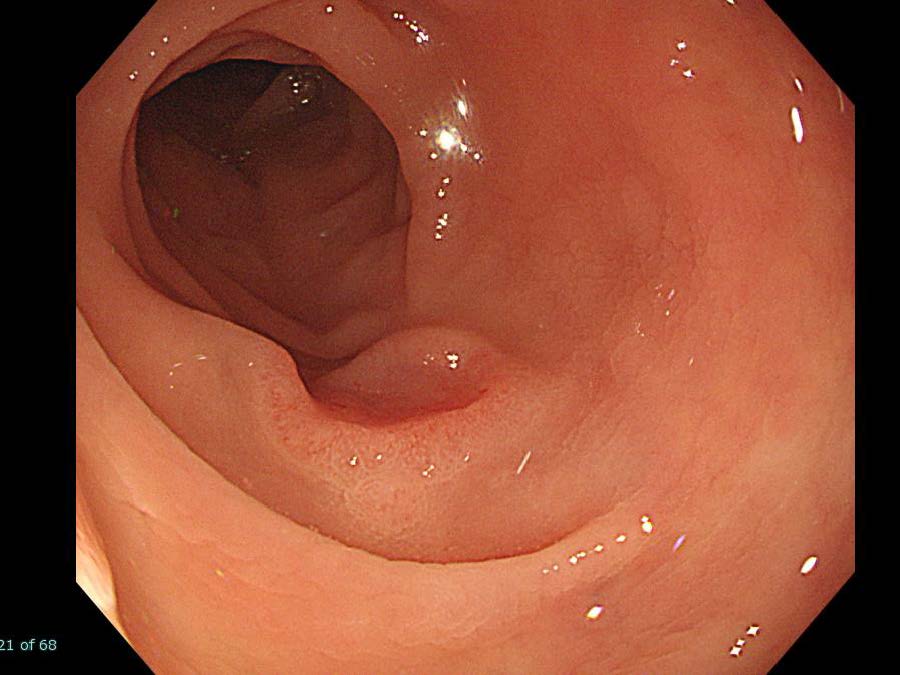

消化管Mapping~大腸~ 2021.10.27

消化管Mapping~大腸~

内視鏡検査・治療

消化管Mapping